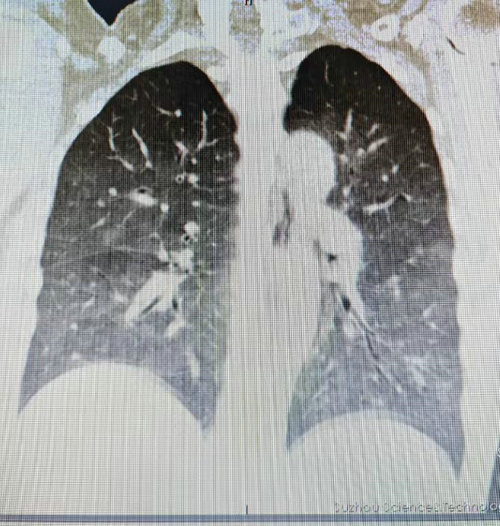

入院完善肺部CT检查结果提示李阿姨的肺部呈现“白肺”改变,病情迅速恶化。追问病史得知,李阿姨既往患有类风湿性关节炎,长期间断性口服激素类药物及免疫抑制剂,这使得她的免疫系统极为脆弱,为病原体的侵袭埋下了隐患。